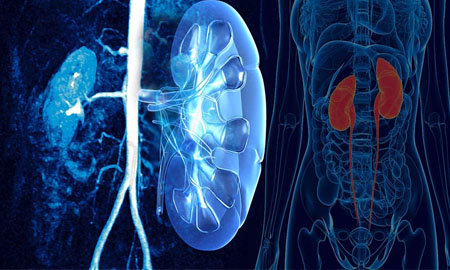

Iniya Hospital specializes in the treatment General Surgery. We have highly skilled personnel, the latest state of the art equipment, and convenient hours. We strive to satisfy every patient’s needs with comprehensive, sensitive, and cost effective care. Treating all kinds of General Surgery, Laparoscopy, General medicine, Neuro Medicine, Paediatric Medicine and Surgery, Surgical Oncology, Plastic Surgery, Urology, Orthopaedics, ENT and Dental, Skin , Physio- Theraphy. All neonatal and paediatric patients are also being treated here.. With you’ll receive the highly qualified care from our warm staff.